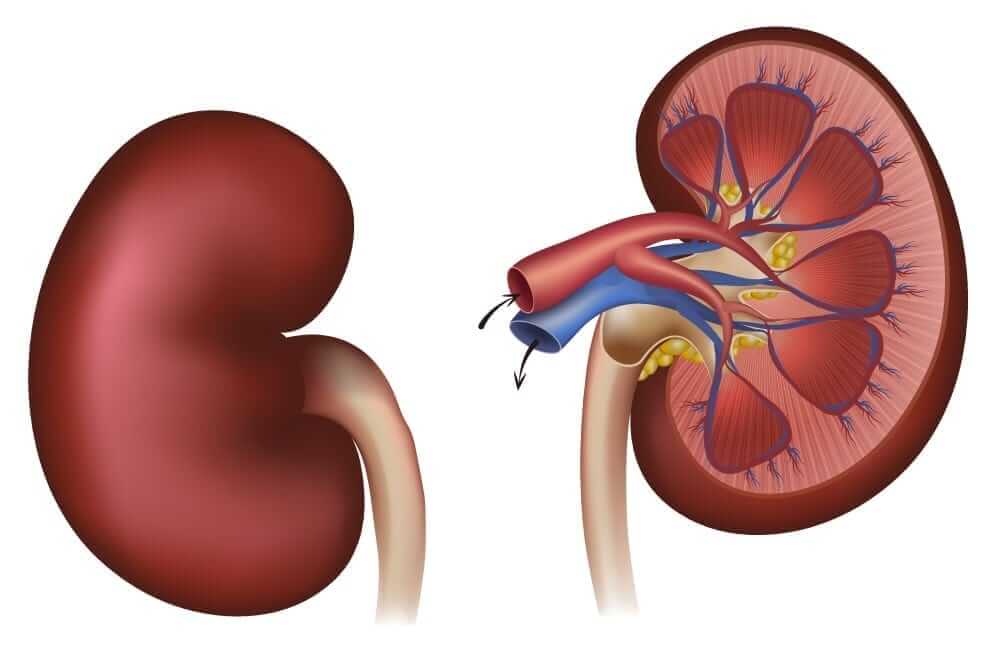

Строение почек человека: Фото и описание